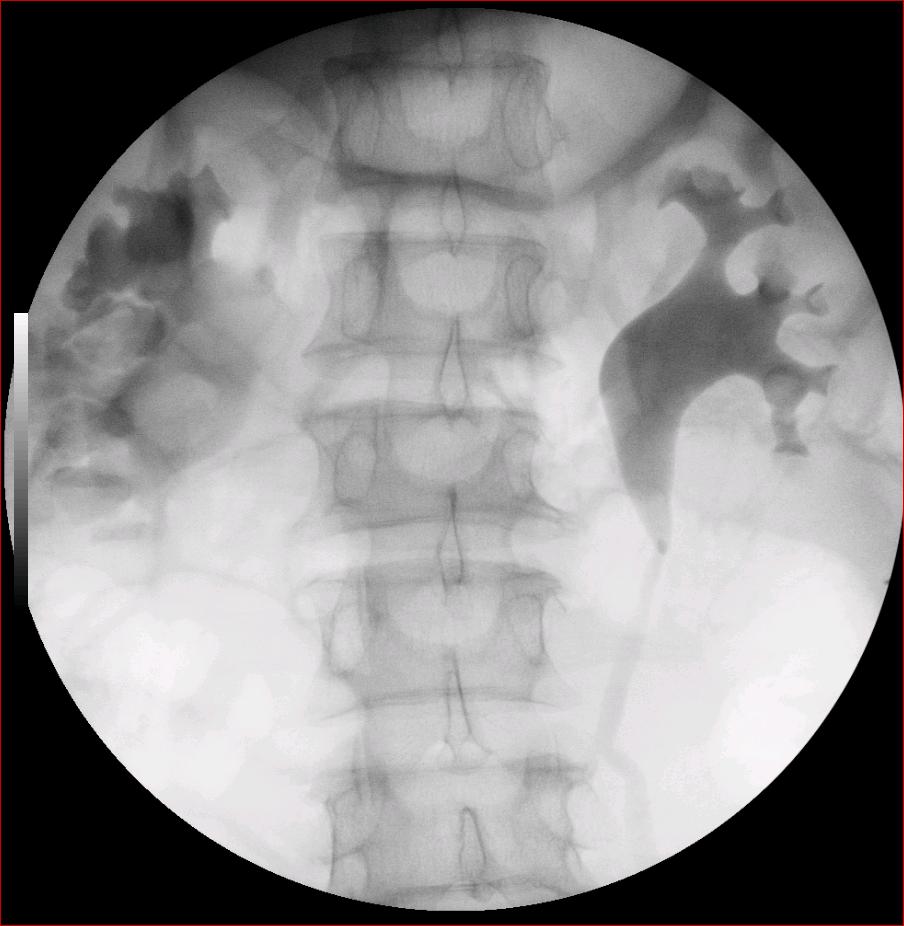

以下是引用luoxinjun在2008-2-18 15:54:00的发言:[br]右肾积水,右输尿管下端结石

以下是引用zhangxiangjun在2008-2-18 21:01:00的发言:[br]右输尿管盆段末端结石,继发其近端输尿管、右肾积水。

以下是引用hexue在2008-2-18 17:33:00的发言:[br]右输尿管下段结石并右肾及右输尿管积水扩张

以下是引用杀毒软件在2008-2-18 16:24:00的发言:[br]右输尿管下段结石,肾盂积水。